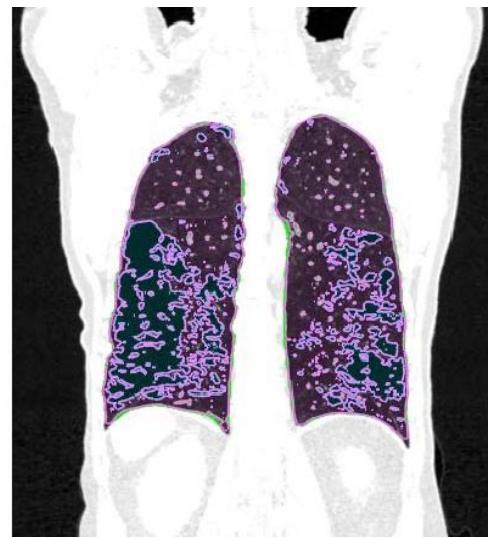

In patients with lung cancer who are candidates for radiotherapy treatment, densitometry provides additional information about the patient's clinical condition (14,15), in addition to the possibility of visually mapping the whole lung tissue and its different densities (figure 1).

Figure 1: Visual representation of emphysema (blue), normal tissue (pink), and fibrosis (green)